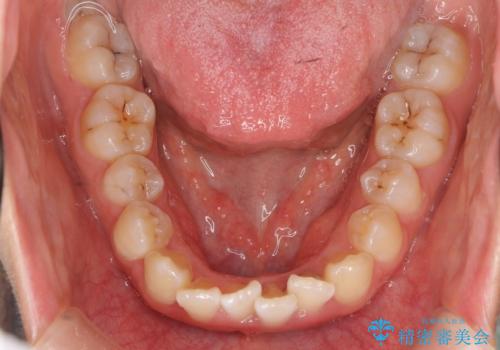

上下の前歯のがたつき 歯を抜かずに矯正

- 上下の前歯のがたつきを主訴に来院。

歯を抜かずに前歯を揃えています。

奥歯を後ろに下げたりなどはしていません。

奥歯を外に広げ、前歯中心に歯を少し削っていますが、健康には問題ない範囲で行なっています。